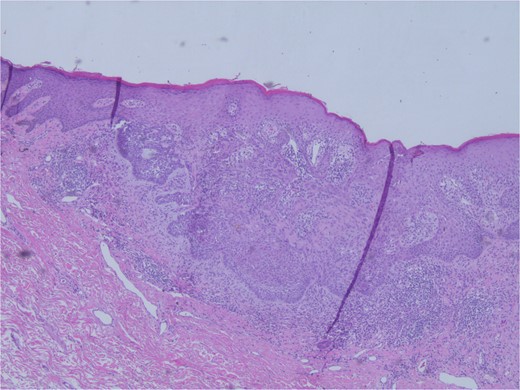

At the time of the surgery, the lesion was excised with 5 mm margins, given the acceptable margins of 4 mm for nonmelanoma skin cancer [4]. Macroscopic examination of the lesion revealed a well-defined, hyperpigmented, macular lesion with pathology positive for infiltrating BSC with negative margins confirmed on histology. Histology was notable for predominantly basal cell morphology with areas of squamous differentiation. The presence of the basal cell carcinoma component is demonstrated (Fig. 1). The BSC with abnormal squamous keratinization is also demonstrated (Figs 2–4). These studies were conducted on routine hematoxylin and eosin stains confirming the diagnosis of BSC. The patient was seen in the office, and at 2 months postoperative, there were no clinical concerns.

Microphotograph revealing basal cell carcinoma component on histology.